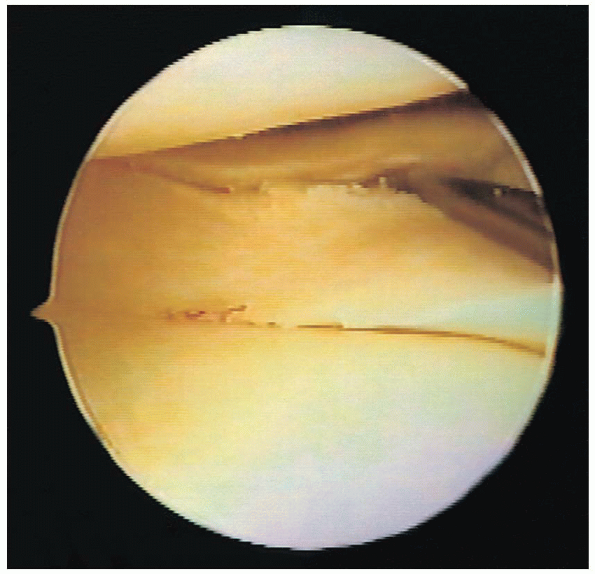

lateral compartment (Fig. 25-19). The arthroscopic camera should be rotated in conjunction with the knee as it is placed into this position. Downward pressure on the thigh helps to open the lateral compartment. The lateral meniscus is inspected and palpated throughout its entire length (Fig. 25-20).

FIGURE 25-20.

Visualization of the posterior horn of the lateral meniscus, demonstrating a tear. The probe is placed in the superior surface of the tear. |